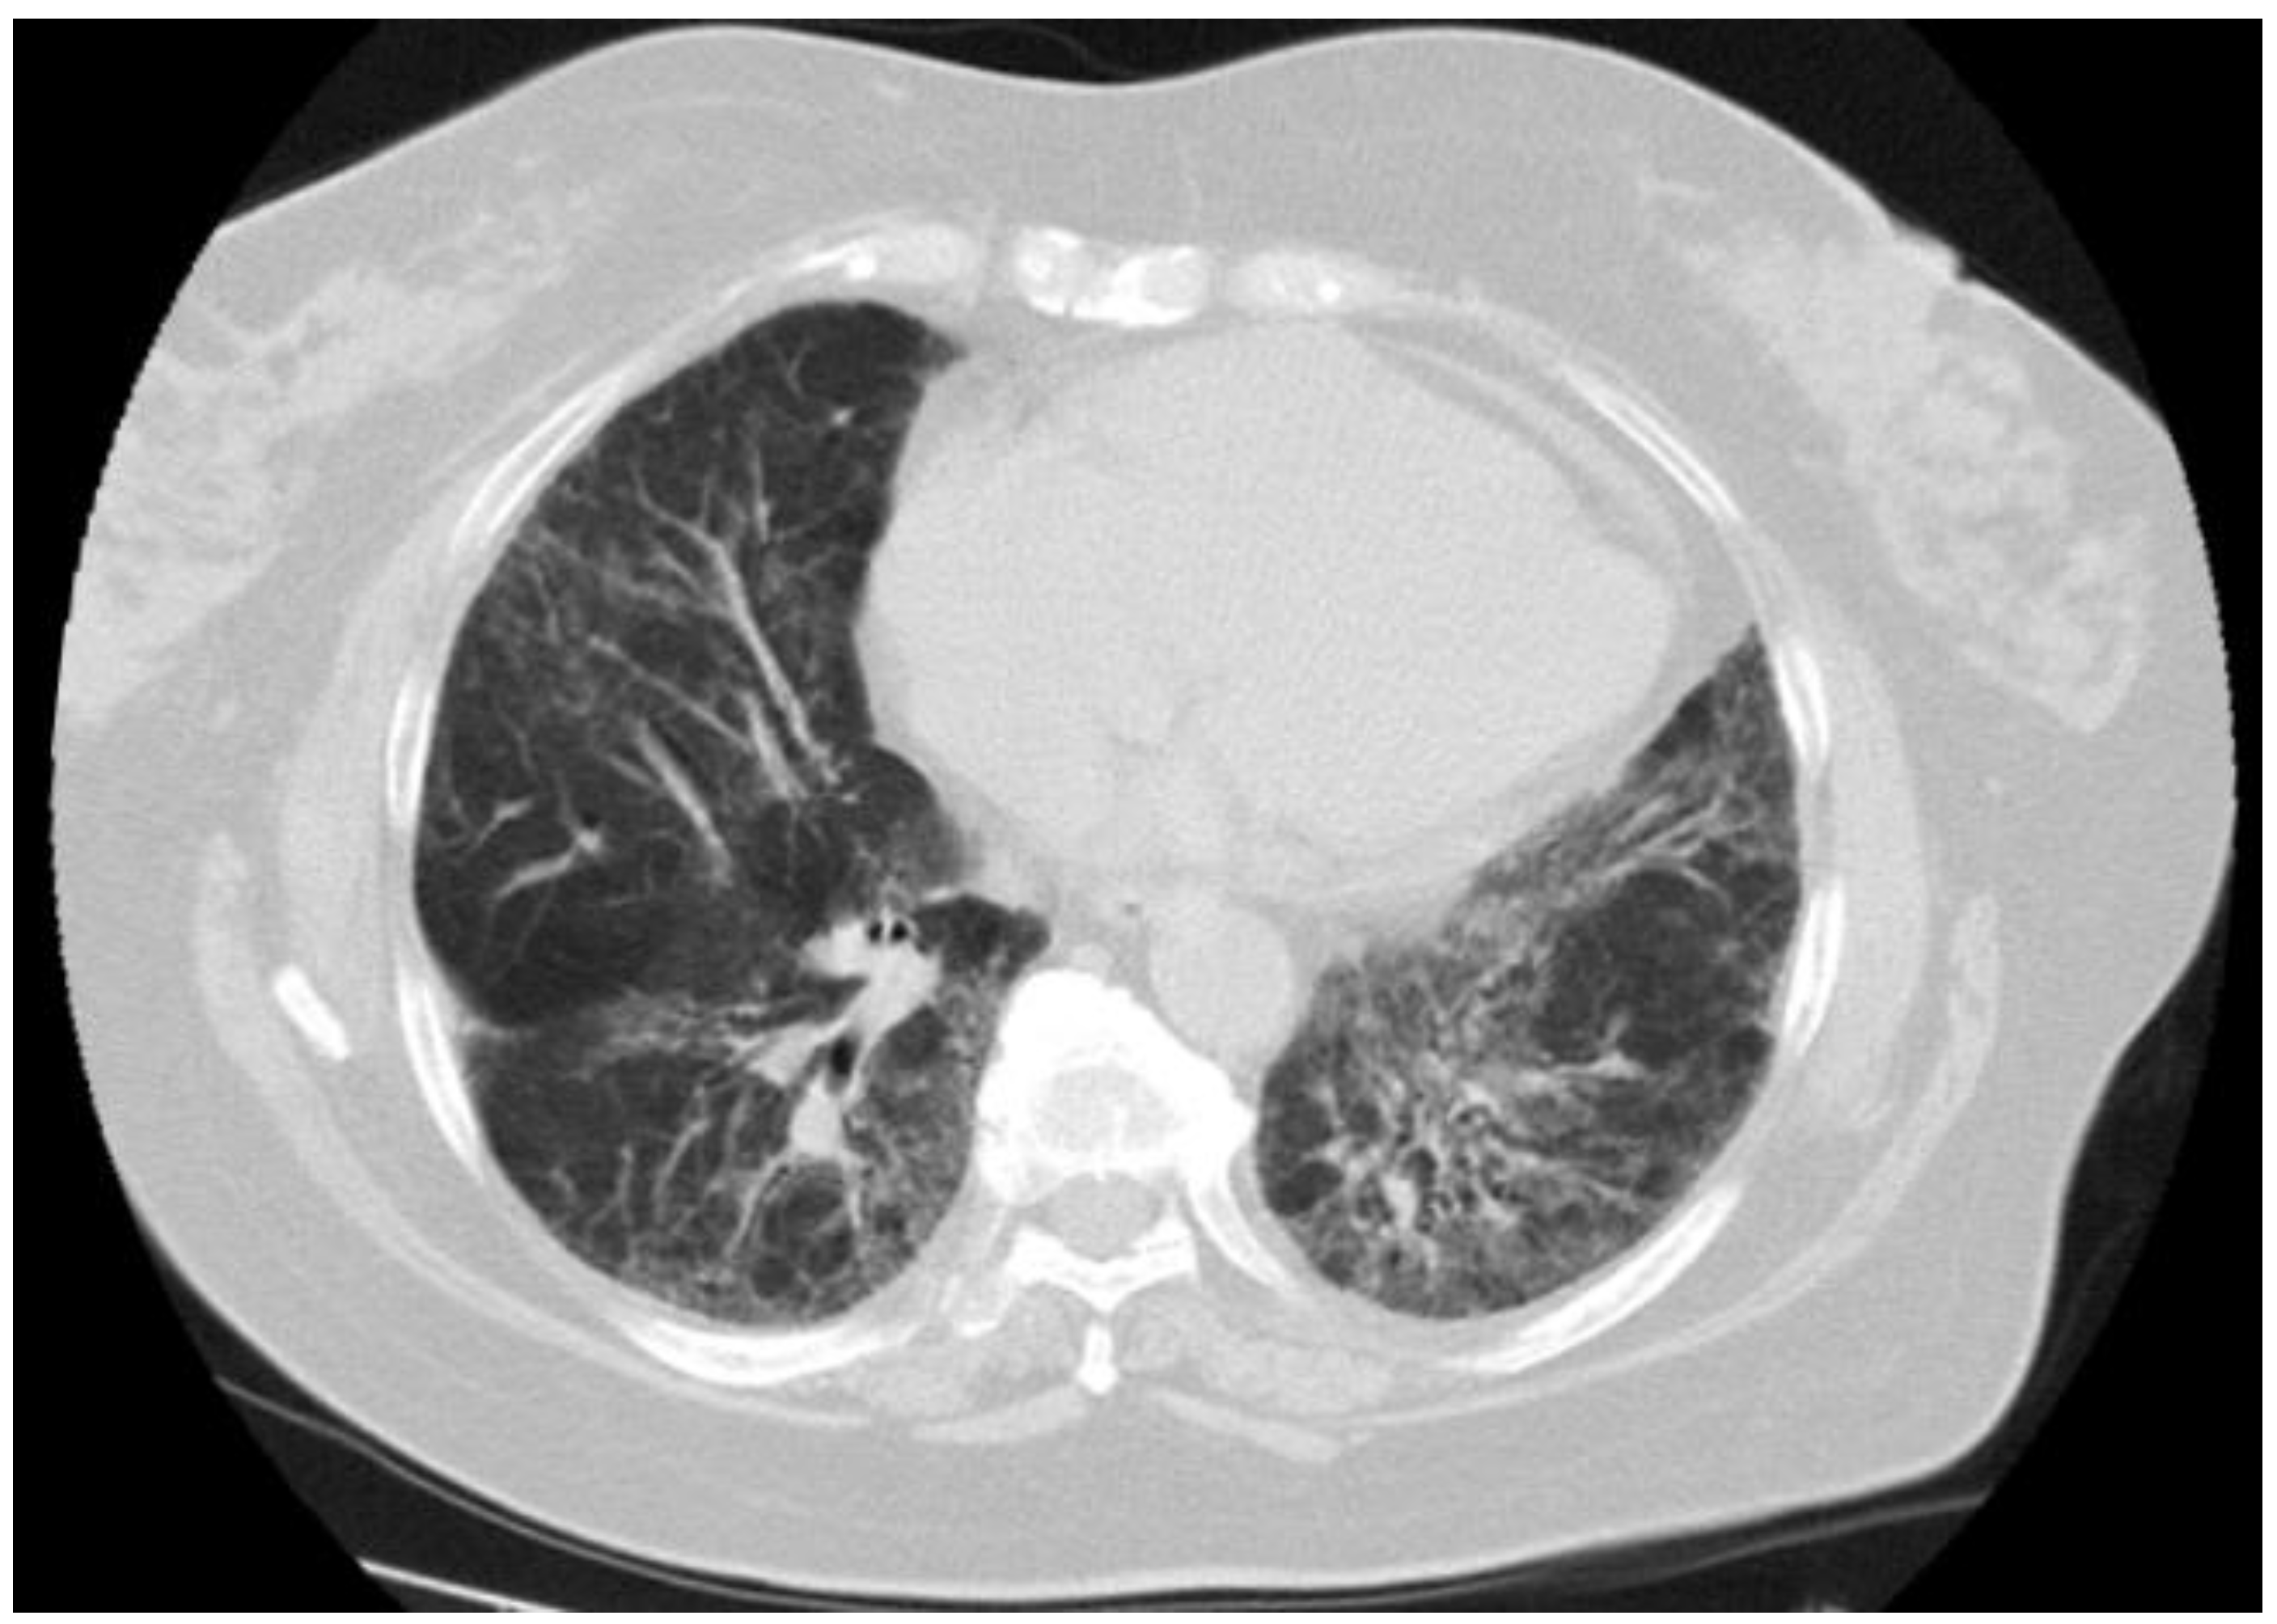

Tissue histology was available in 9 of 14 patients with sarcoid-like patterns (lung biopsy via video-assisted thoracoscopic surgery in five, mediastinal lymph nodes in two, supraclavicular lymph nodes in two), and in all cases showed non-necrotizing epithelioid cell granulomas with giant cells. An open lung biopsy was performed on two patients with pulmonary consolidation showed granulation tissue buds in the alveoli and alveolar ductus consistent with the OP pattern. Histopathological findings in three patients with indeterminate radiological patterns included dense lymphocytic infiltration of the alveolar septa (n = 3), giant cells (n = 3), poorly formed non-necrotizing epithelioid cell granulomas (n = 2), foamy macrophages (n = 2), mild eosinophilic infiltrate (n = 2) and moderate interstitial fibrosis (n = 1). These findings were incompatible with radiological data, and we were unable to define a type of ILD. One patient with an unclassifiable radiological pattern refused a lung biopsy. Representative HRCT patterns and tissue histology are shown in Figure 2, Figure 3, Figure 4 and Figure 5.

Repeated chest HRCT was conducted in 34 patients with ILD at an interval of 3–6 months. Immunosuppressive agents were started in case of radiological and/or clinical deterioration of ILD. A total of 16 patients were treated for ILD with azathioprine or methotrexate in combination with systemic glucocorticoid. Improvement in chest HRCT was shown in 22 patients. It was spontaneous in eight patients (sarcoid-like pattern in three, subclinical ILD in three, and OP in two) or induced by immunosuppression in 14 patients (sarcoid-like pattern in eight, OP in four, UnIP in two). ILD was stable in fivepatients who received no immunosuppression (subclinical ILD in fourand sarcoid-like pattern in one) and in two patients treated with immunosuppressive agents (sarcoid-like pattern and UIP). Radiological progression of ILD was found in five patients. Two patients with NSIP and UnIP died from liver cirrhosis complications before initiation of immunosuppressive treatment, whereas two patients with OP and UnIP had no respiratory symptoms and were clinically stable. One patient showed no ILD response to immunosuppressive agents. This was a 70-year-old female with NSIP (Figure 2) who developed severe pulmonary hypertension and died from respiratory failure. The autopsy revealed extensive interstitial pulmonary fibrosis consistent with fibrosing NSIP. During follow-up, only this patient died from ILD complications.

Figure 2. NSIP pattern in a 70-year-old female with PBC who died from progressive respiratory failure.